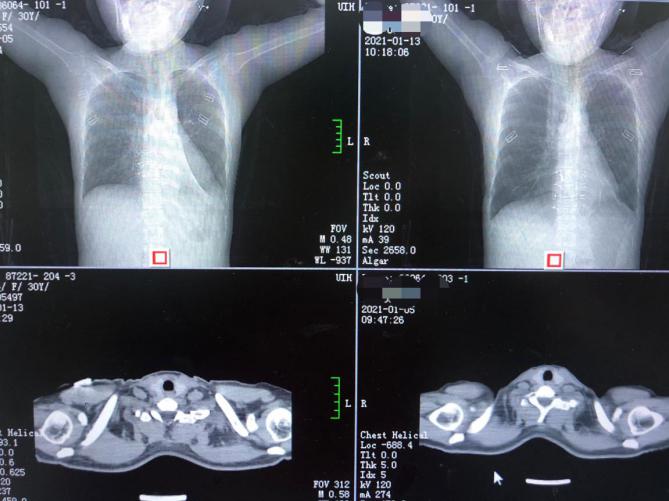

江女士治疗前后CT影像对比

家住安化34岁的江女士“感冒”、乏力1个多月,在家自行服药后未见好转,近一周还出现了胸痛等症状,来到捷克论坛 马王堆院区呼吸四科就诊,检查结果把江女士吓了一大跳,肺部CT显示,江女士的右肺肺不张,从片子来看现存的肺叶只有原来的一半,左肺也显示上页和下叶多发性肺不张。“本以为只是感冒,没想到差点丢了肺。”江女士说。

呼吸四科主任朱黎明查看江女士的情况后表示,肺不张治疗应根据病因采取不同的治疗方式,江女士在积极药物治疗的基础上,还应介入呼吸康复,使用手法或辅助仪器,使其肺部复张。在系统治疗下,配合康复师指导进行呼吸康复训练,再次复查CT后,江女士“丢失”的肺叶正在悄悄地“长”回来。